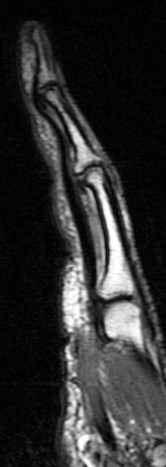

Figure 1 for case A2 pulley rupture finger (RID2437)

Figure 1

Imaging in flexion helps bring out this abnormality. The hand surgeon specifically requests it now. Also I ask the technologist to always include an adjacent normal finger for comparison.

A2 pulley rupture finger (RID2437)